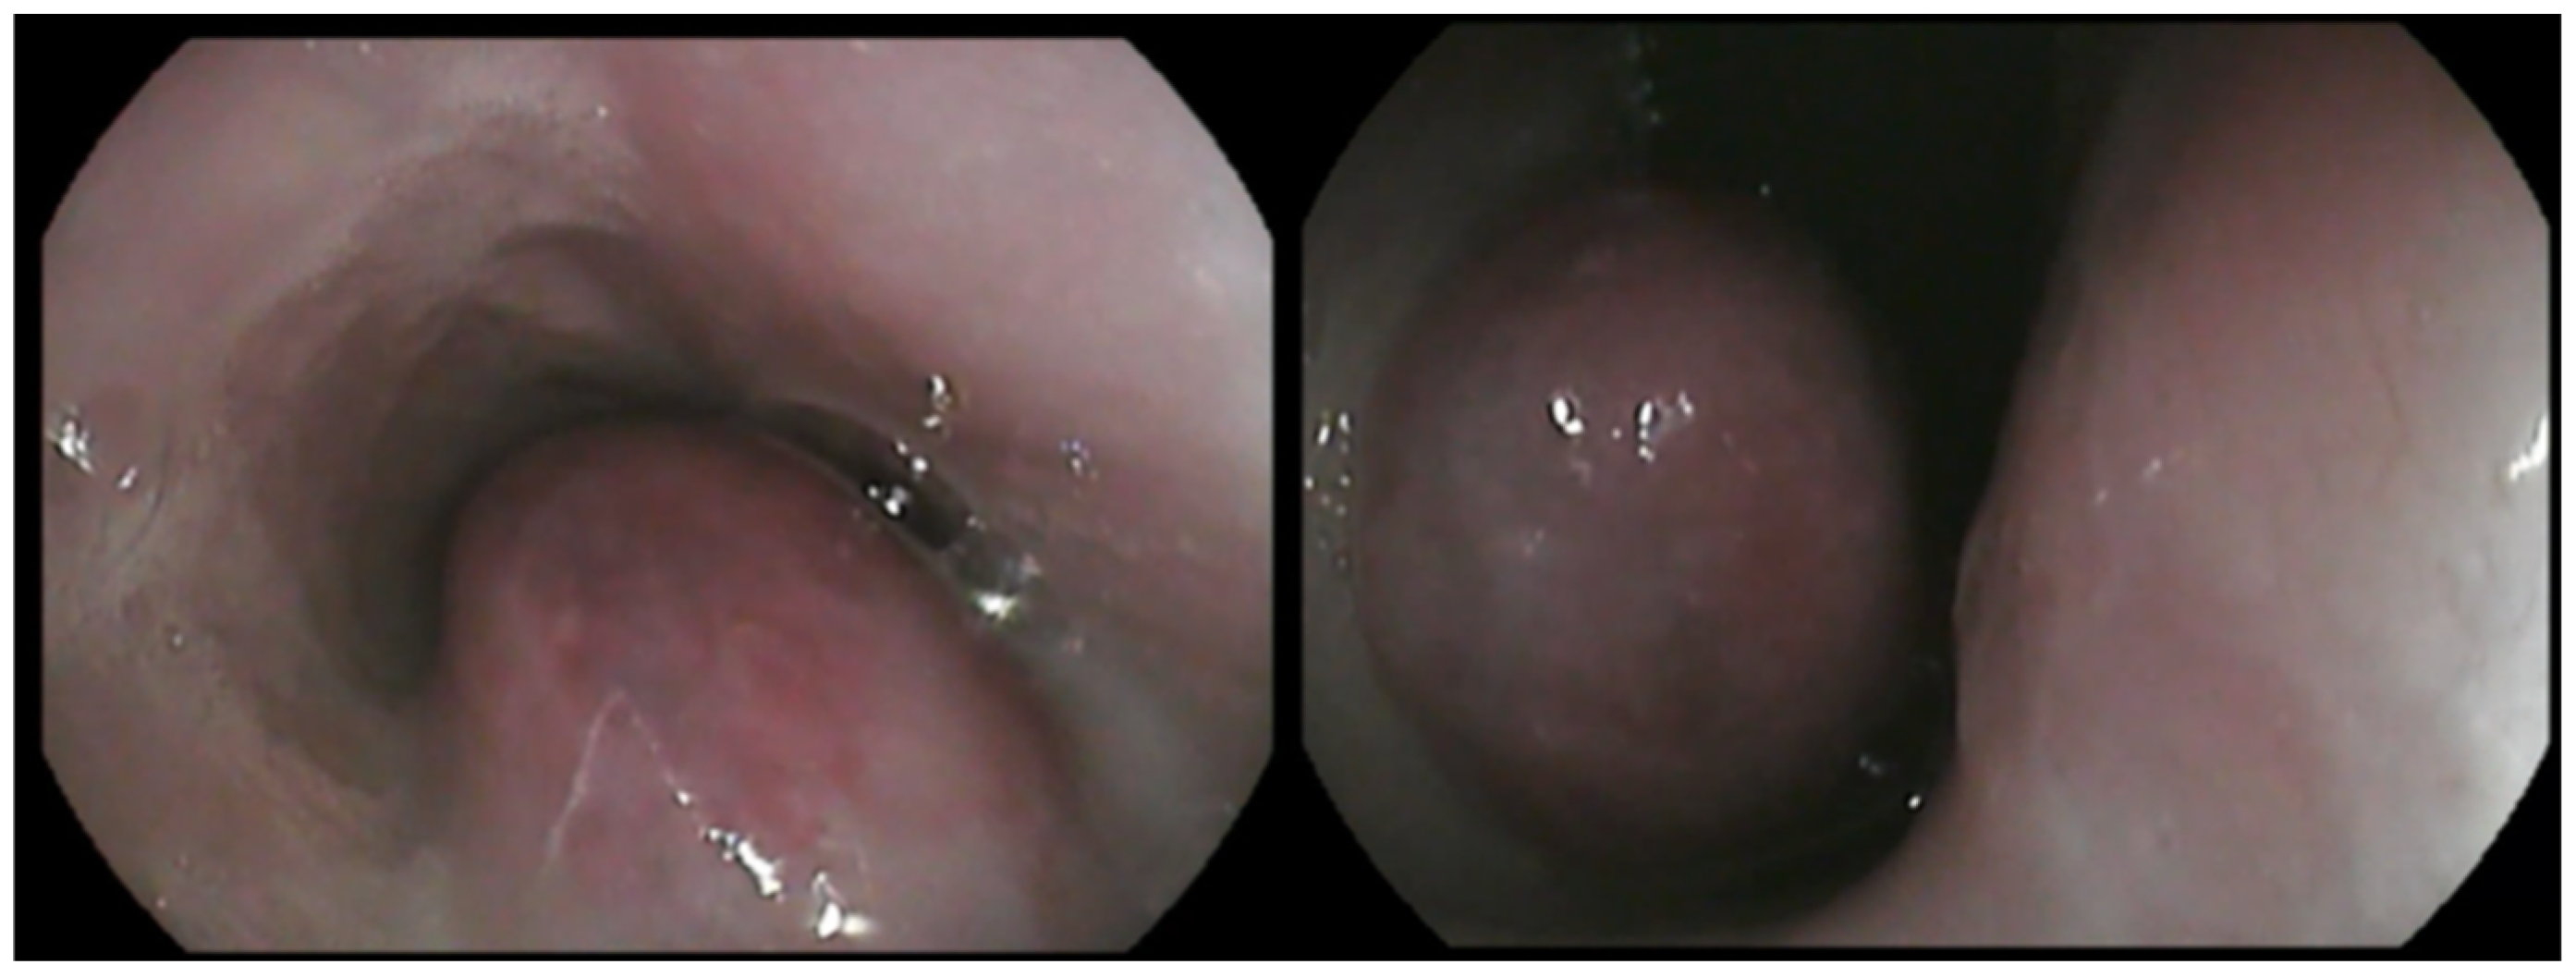

Follow-up esophagoscopies were performed every 3–6 months after surgical excision and did not show evidence of tumor regrowth in the esophagus until 18 months after surgery, when recurrence of the mass was identified (Figure 10). The dog still remains asymptomatic, with the exception of one episode of vomiting and regurgitation, which was resolved after symptomatic treatment.

Figure 10.

Macroscopic view of the esophageal lumen during follow-up esophagoscopy. Notice a regrowth of the mass (18 months after the surgical excision).